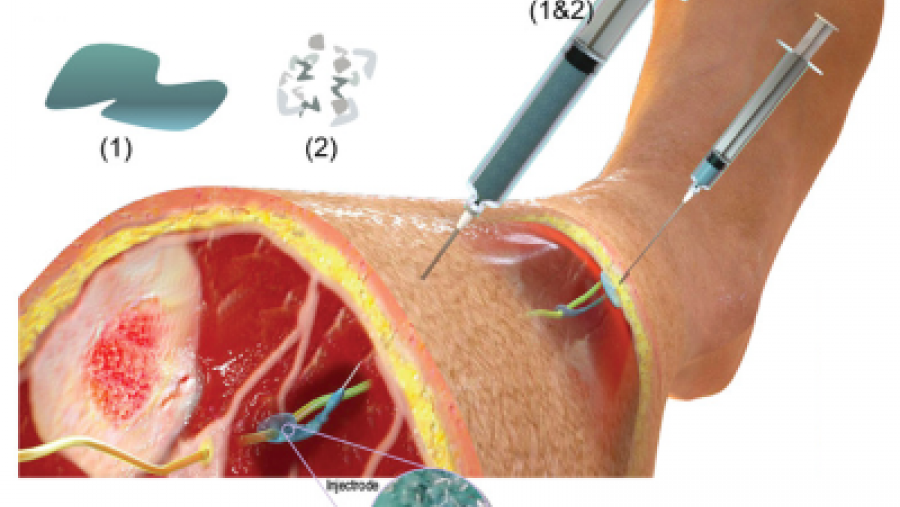

Researchers develop a new type of injectable electrode for neuromodulation therapy.

Published: June 10, 2020

Topics:

Device Discovery